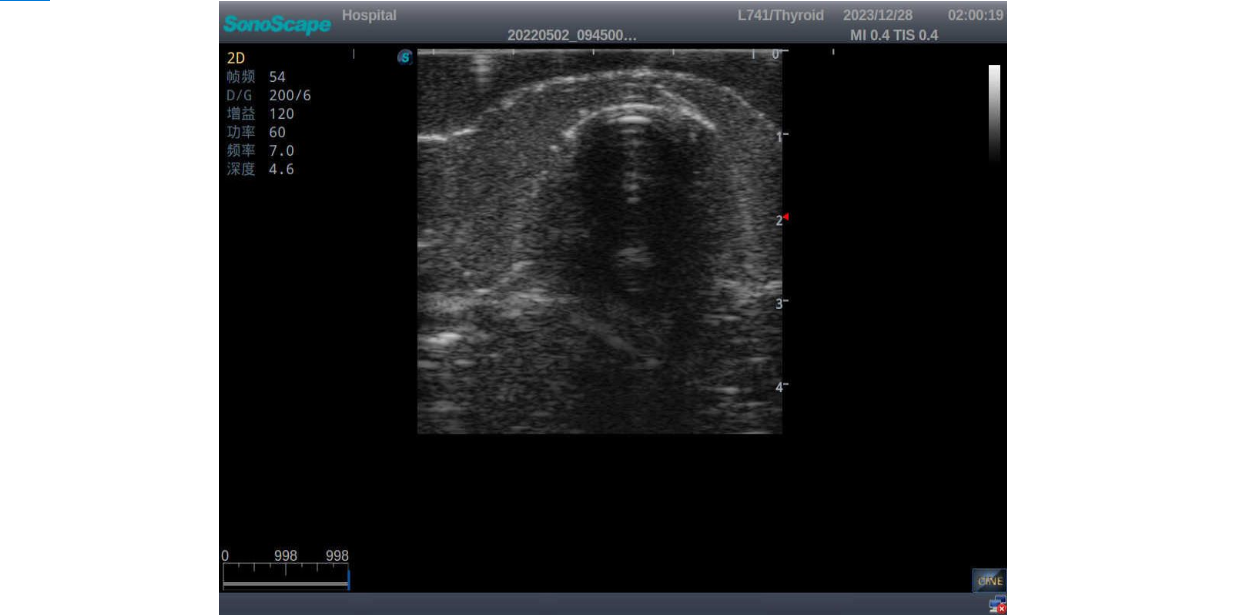

3) It comes with four (4) thyroid modules and can show five (5) ultrasonic images: normal thyroid, thyroid adenoma, thyroid cancer, nodular goiter, thyroid cyst

Normal thyroid with homogeneous parenchymal echo and well-defined capsule

Thyroid adenoma with well-defined border and smooth uniform halo

Thyroid cancer with irregular mass, unclear border, uneven internal echo or calcification strong echoes

Nodular goiter with irregular border and varying sizes of low echo, isoechoic, or high echo nodules

Thyroid cyst, which fluid area, dark and echo-free area can be seen